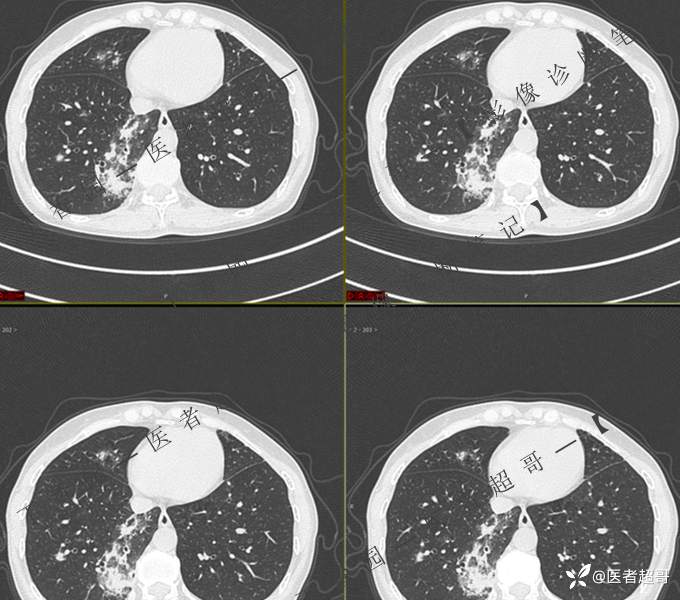

2402胸部影像病例︱持续追踪的一个患者,时间轴较长,闭卷分析,请畅所欲言~~~

女性,57岁

主 诉:发热伴咳嗽咳痰1周

现病史:1周前患者无明显原因及诱因出现发热,最高体温39.0℃,伴咳嗽后胸痛及全身酸痛,伴咳嗽,流涕,伴痰中带有血丝,鲜红色,无背板、头晕、头痛、恶心、呕吐,患者未就诊于医院,行“川贝止咳”,未服用抗生素,后于1天前就诊于我院门诊,现为行进一步治疗,入住我科,患者自起病以来,精神饮食可,大小便正常。

第一次检查